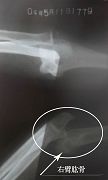

当天半夜我离开家以后,不断更换住处。三月二十九日那天,我刚把房门裂个缝,就见一个贼头贼脑的人正往我这里看,极度的恐惧顿时吓的我不知所措,只想快点离开住处,从窗往外看楼与地面并不高,我就跳了下来,结果受了伤,过路人把我抬到一辆出租车上,当司机知道我的遭遇时他什么都没说,把我送到了一个法轮功学员家。历经一个多月艰难的日子我终于能行走了,那段日子没有医疗(不敢住院怕被绑架),没有家人,只有痛苦和恐惧,若不是有大法的法理、同修的照顾真的很难走过来。后来到医院确诊我的右胳膊肘到手的那段骨头从胳膊肘里撞出来了,胸椎十二节和腰椎一节压缩性骨折,后来成为两椎体融合成一个椎体,当医生看到X光片子惊讶的说:“这是要瘫痪的!”当时腰椎骨折手术得十万余元,我被单位开除,没有生活来源,没钱医治。也只能在弟、妹的援助下做了胳膊的手术,术后胳膊再也不能直伸了,腰部连洗衣服都疼,更不能干重活,终生残疾。

吴旭姝胳膊和腰椎的X光片